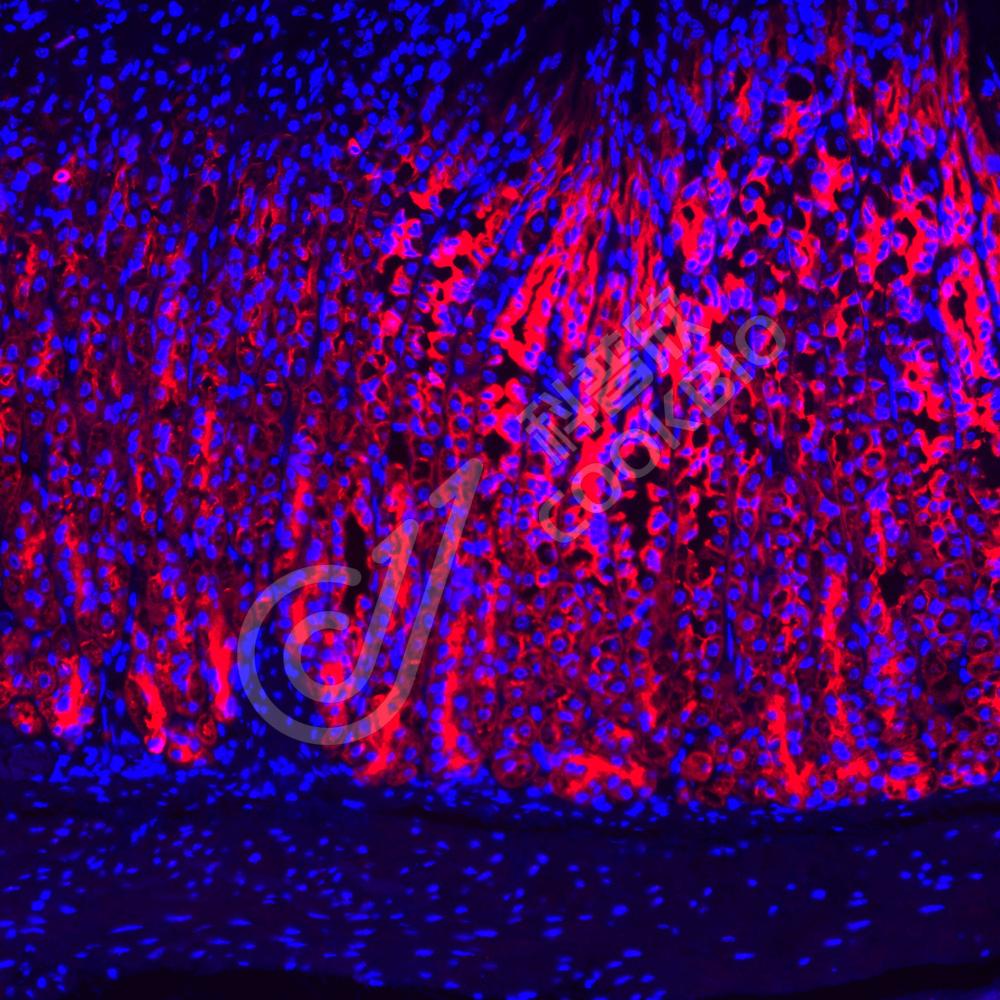

IF检测Cytokeratin 8蛋白(货号 K133693)(红色).

样品: 小鼠小肠, 4%多聚甲醛 (货号KSG1101) 固定12-24小时.

抗原修复: Tris-EDTA抗原修复液(pH 9.0) (KSG1203), 98℃, 20分钟.

封闭: 3% BSA(货号KSGC305010)的PBS溶液, 室温孵育30分钟.

—抗: 1: 600稀释, 4℃ 孵育过夜.

二抗: Cy3标记山羊抗兔IgG (H+L) (货号KB63909), 1: 300稀释, 室温孵育1小时.